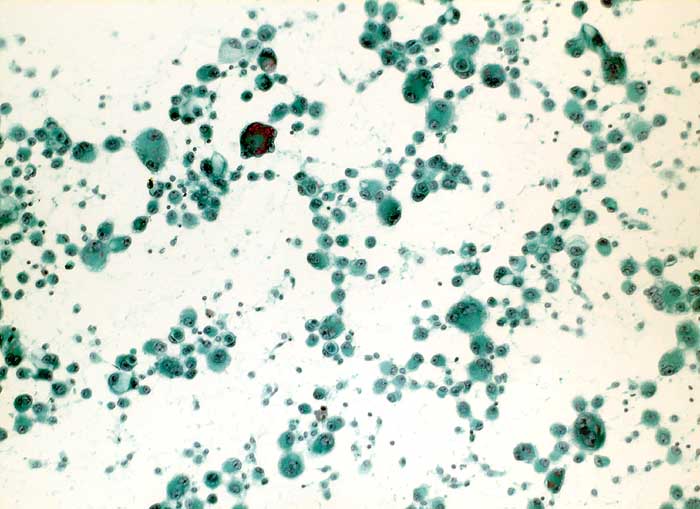

nicht kleinzelliges Bronchuskarzinom

Pleuraerguss Zytologie

Pleuraerguss: massenhaft Zellen eines Adenokarzinoms. Die extreme Polymorphie mit sehr unterschiedlich grossen Tumorzellen passt zu einem primären Lungenkarzinom.

Metastasierendes Bronchuskarzinom

Zytologie

100